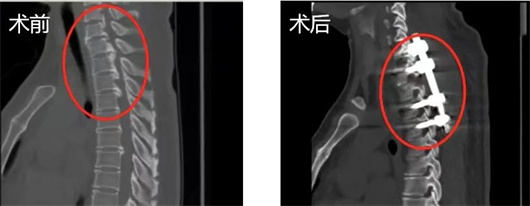

第五集 挺直

“我可能从胸椎以下就瘫痪了”

居住在云南昆明的黄丕燕

一周内突然无法行走

被确诊患有严重的胸椎管狭窄症

手术风险和致残率非常高

情况更为特殊的是

致压物位于上胸椎

不仅周围血管更加薄弱

还要从脊髓后方绕到前方进行切除

使问题更为棘手

骨科主任李危石教授团队

成功为患者实施上胸椎椎管后壁切除术

帮助患者从无法行走到行动自如

这是脊椎外科医生最愿意看到的